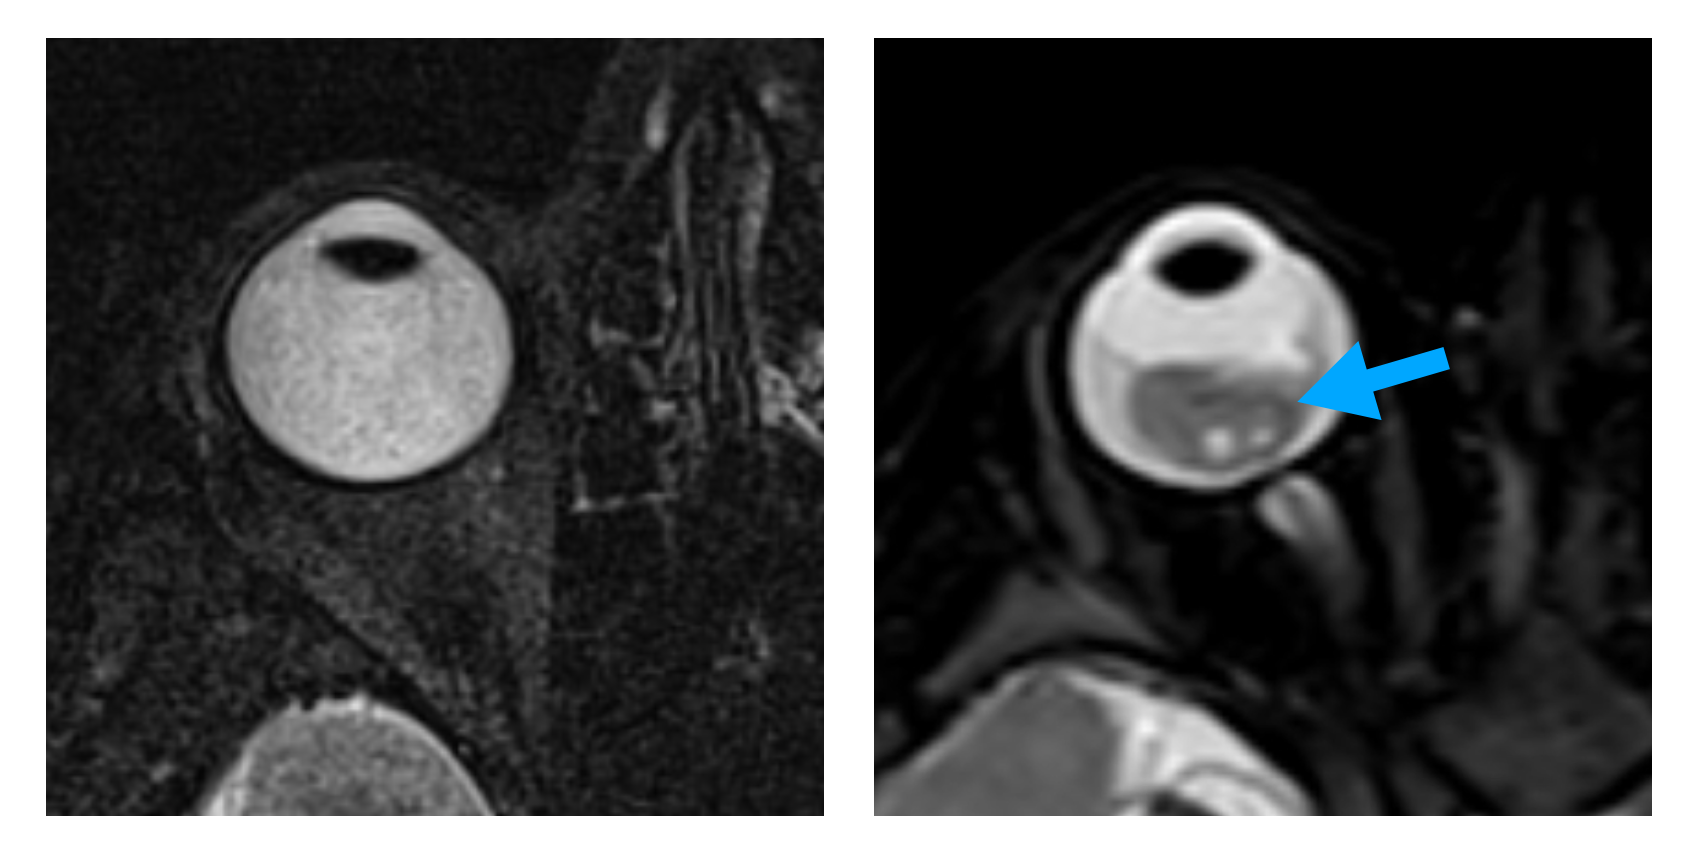

Imagem de Ressonância Magnética mostrando olho normal à esquerda e olho afetado pelo Retinoblastoma, apontado pela seta azul.